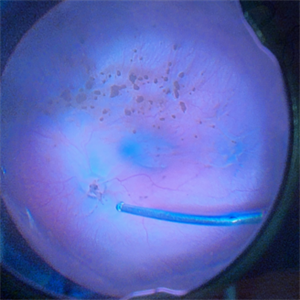

Familial Exudative Vitreoretinopathy with Cataract

FEVR in a monocular patient with dense posterior subcapsular cataract.

Photographer: Corina Skrezk / Hospital de Olhos do Paraná

Condition/keywords: familial exudative vitreoretinopathy (FEVR), Optos